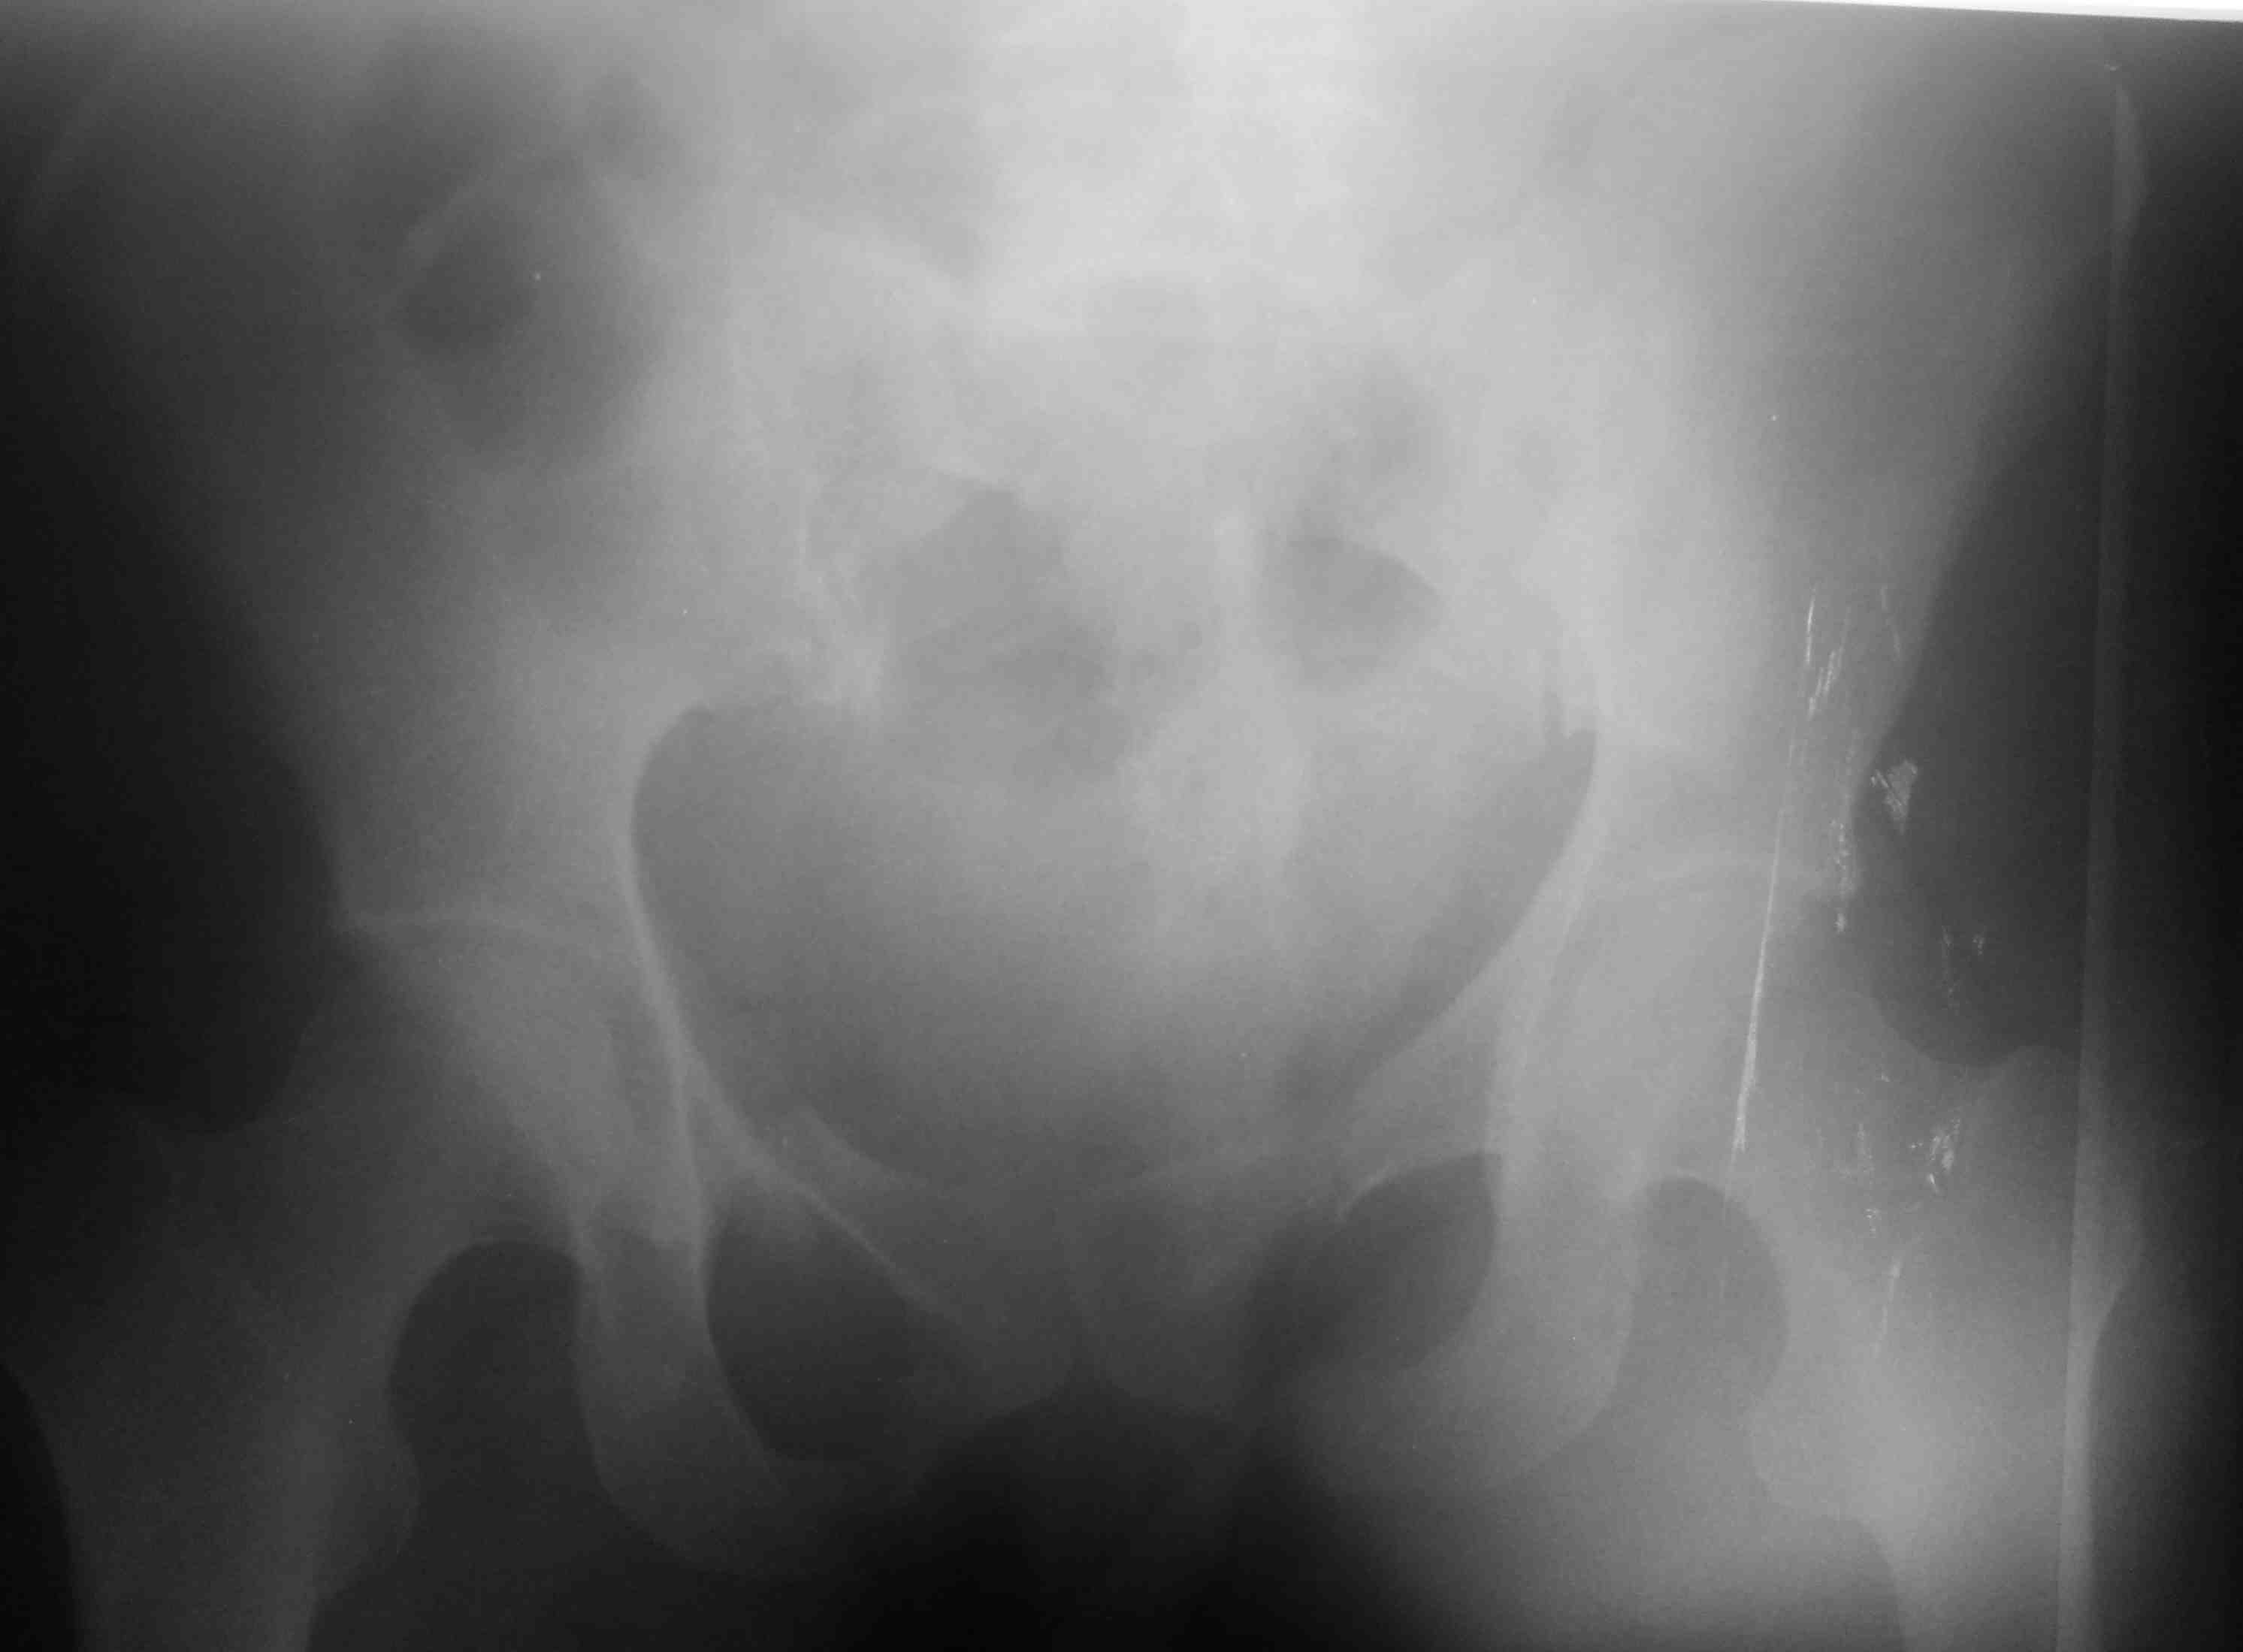

[Ortho] тяжелый таз

высылаю контрольные снимки на вытяжении, правую половину таза

подрепонировали вручную, за лево - скелетка. Дополнительно, левое плечо

- диафиз, множественные переломы ребер слева. Стала хуже по легким. Пока

план - при улучшении по легким - передняя рама + илиосакральные винты

справа, при улучшении - расслабляем переднюю раму, открыто синтезируем

подвздошную кость задним доступом, обратно затягиваем аппарат. Плечо -

когда получится